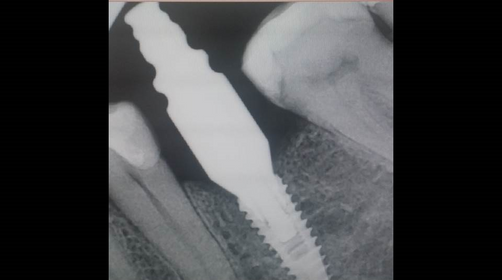

6 months follow-up of #36 implant placementDr. Pavel YaroshevichJul 2, 20151 min readPre-operative Observation- One year after the extraction of #36 Post-operative radiological view.After 10 weeks.6 Months follow-up